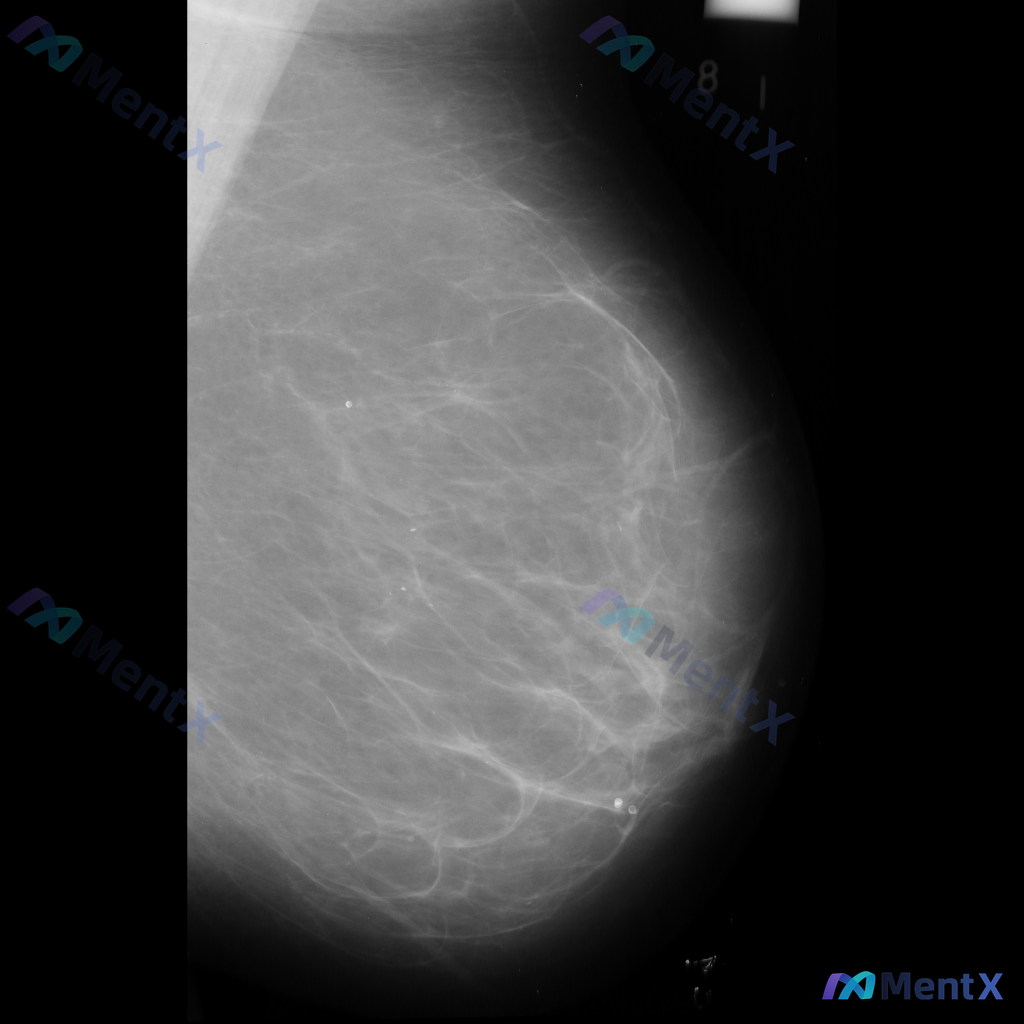

整理到一张乳腺钼靶影像的异常表现,分享给大家讨论: 一侧乳腺可见不规则形高密度致密影,伴有明显的结构扭曲和局部腺体结构紊乱。 单看这组影像描述,大家会优先往哪种方向考虑?后续如果要进一步明确,你觉得哪些步骤比较关键?